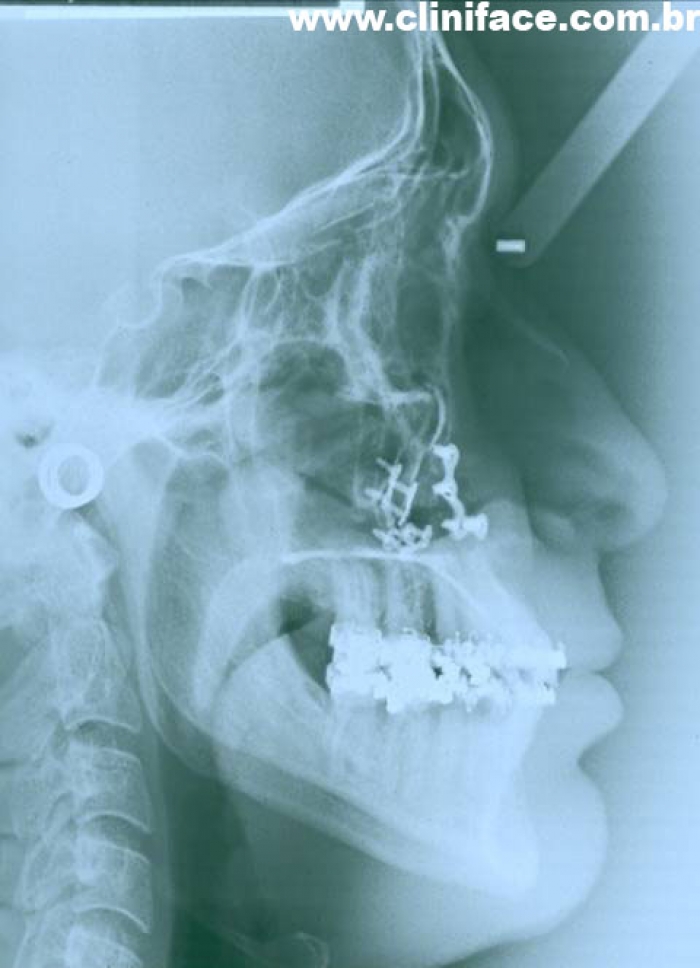

Telerradiografia final